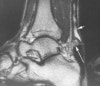

MRI : 아킬레스건 파열(Achilles tendon interstitial tears)

T1 강조 영상에서 세로 방향의 내부 신호 변화가 처음으로 보입니다.

이러한 파열이 더 심각해지면, T2 강조영상에서 또한 비정상적으로 나타납니다.

Partial tear : 수평 방향의 신호 이상이 나타납니다.